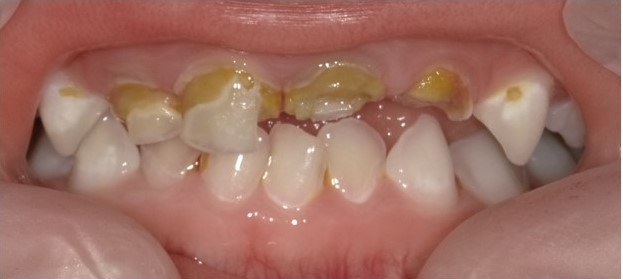

①哺乳う蝕

糖分を多量に含んでいる母乳を寝かしつけながら飲ませることで生じるう蝕のことを「哺乳う蝕」と呼んでいます。1歳半頃までにスムーズに卒乳できればよいのですが、就寝時にぐずったりすると根負けしてしまい、卒乳の時期が遅くなってしまうことがあります。哺乳う蝕では、一般的にう蝕にならない下顎前歯部までも侵されてしまうことが特徴であり、3歳以前に多くの歯にう蝕が発生してしまいます(図4)。そこで、1歳代のお子さんの保護者と接する機会があれば、卒乳に関して話題にしていただくのがよいと思います。また、「哺乳瓶う蝕」という用語もあります。これは、哺乳瓶に糖分を多量に含んでいる飲料を入れて与えることで生じるう蝕です。長時間にわたって砂糖を含む飲料を摂取することになるため、哺乳う蝕と同様に、低年齢にも関わらず多くの歯にう蝕が生じます。

(図4)哺乳う蝕の一例(2歳6か月男児)